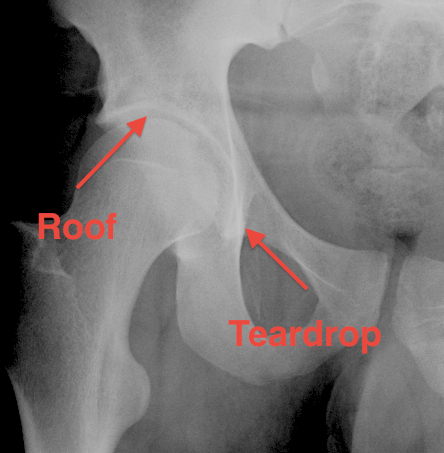

3. The Teardrop

- lateral: subchondral bone condensation at anterior margin of cotyloid fossa

- medial: anterior flat part of quadrilateral surface of iliac bone

4. Roof of acetabulum